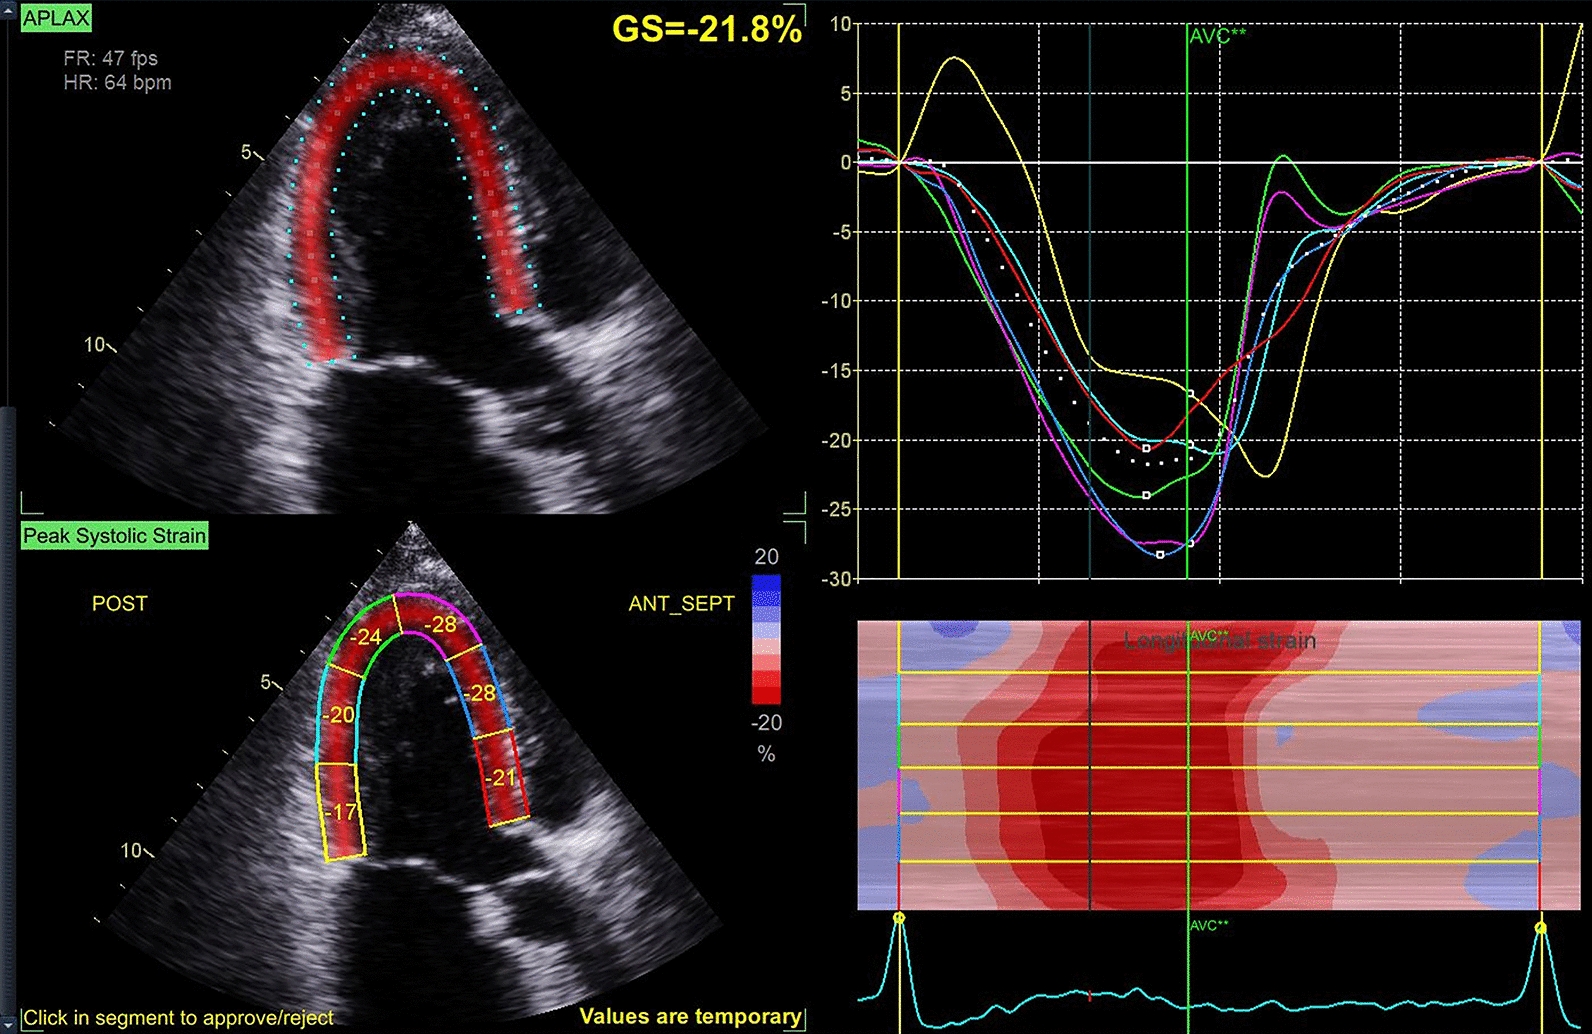

Methods: We conducted a retrospective analysis of 128 non-valvular AF patients between January 2023 and January 2025. Patients were classified into PAF (n = 77) and PsAF (n = 51) groups based on preoperative 24-h Holter monitoring. Speckle-tracking echocardiography was used to assess myocardial strain. Multivariate linear regression models were constructed to evaluate the association between AF subtype and the global longitudinal peak strain average (GLPS_AVG). Subgroup analyses were conducted across age, gender, BMI, hypertension, hypertriglyceridemia and diabetes.

Results: Patients with PsAF exhibited significantly lower GLPS_AVG values compared to those with PAF (- 14.00 ± 3.24 vs. - 17.71 ± 3.07, P < 0.001). In multivariable-adjusted models, PsAF remained independently associated with reduced GLPS_AVG (Model III: β = 2.70, 95% CI 1.11 ~ 4.29, P < 0.001). Subgroup analysis confirmed that this association exists in every subgroups.